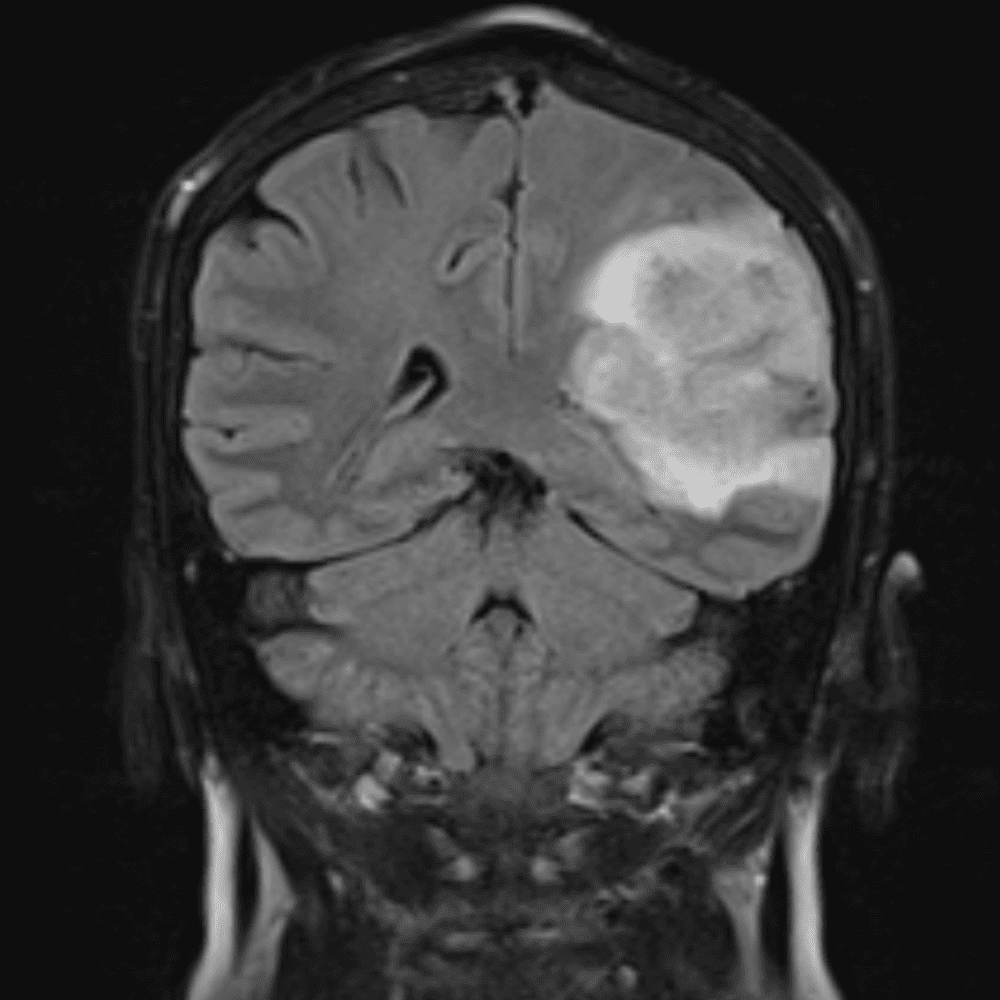

๋‹น์ง ์‹œ ํ”ํžˆ ๋ณผ ์ˆ˜ ์žˆ๋Š” ์‚ฌ๋ก€์˜ ์ „ํ˜•์ ์ธ ์˜ˆ๋ฅผ ํฌํ•จํ•ฉ๋‹ˆ๋‹ค.

39 ์‚ฌ๋ก€

์—ฐ์Šต

๋ฏธ๋ฌ˜ํ•˜๊ฑฐ๋‚˜ ์–ด๋ ค์šด ์‚ฌ๋ก€์™€ ์ผ๋ถ€ ์ •์ƒ ์‚ฌ๋ก€๋ฅผ ํฌํ•จํ•˜์—ฌ ๋‹น์ง์„ ์‹œ๋ฎฌ๋ ˆ์ด์…˜ํ•ฉ๋‹ˆ๋‹ค.

50 ์‚ฌ๋ก€